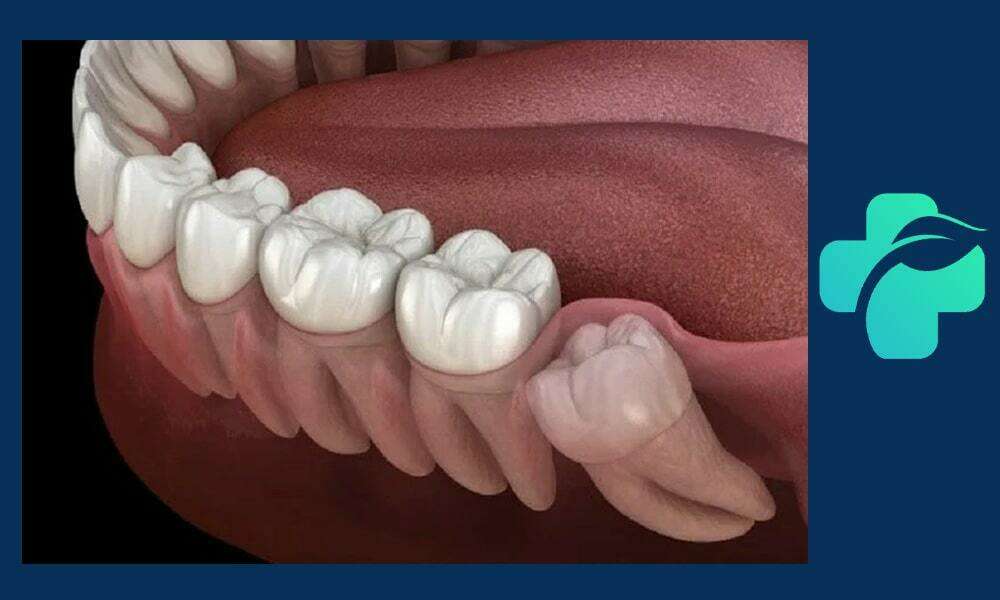

جراحی دندان عقل یکی از عمل های رایج دندانپزشکی است که بسیاری از افراد در دوره ای از زندگی خود به آن نیاز پیدا می کنند. این فرایند، به ویژه زمان هایی که دندان عقل نهفته یا به شکلی پیچیده رشد کرده باشد، دارای اهمیت زیادی است.

گاهی این دندان ها به دلیل نداشتن فضای کافی یا رشد نادرست، دندان عقل نهفته می شوند؛ یعنی به طور کامل یا جزئی از لثه بیرون نزده اند. این وضعیت باعث درد، عفونت، التهاب و حتی آسیب به دندان های مجاور می شود که در این شرایط جراحی دندان عقل ضروری است. اقدام به موقع برای جراحی کشیدن دندان عقل نهفته درد و مشکلات بعدی را به حداقل می رساند.

۲. جراحی دندان عقل نهفته

جراحی دندان عقل نهفته زمانی انجام می شود که دندان داخل لثه گیر کرده و رشد کامل نداشته باشد. در این حالت، دندانپزشک نیاز دارد تا برش لثه ایجاد کرده و در برخی موارد استخوان اطراف دندان را بردارد تا دسترسی به دندان فراهم شود. این نوع جراحی طولانی تر و پیچیده تر از جراحی ساده است و ممکن است با تورم و ناراحتی بیشتری همراه باشد. مراقبت دقیق بعد از جراحی، شامل استفاده از مسکن، رعایت رژیم غذایی نرم و جلوگیری از فشار روی ناحیه جراحی، برای جلوگیری از عفونت و تسریع بهبودی ضروری است. جراحی دندان عقل نهفته اغلب برای پیشگیری از عفونت، درد یا آسیب به دندان های مجاور توصیه می شود.

جراحی دندان عقل پیچیده برای دندان هایی انجام می شود که در زاویه نامناسب، عمیق یا با ساختار استخوانی دشوار قرار دارند. این نوع جراحی نیاز به تخصص بالای جراح دهان و فک دارد و ممکن است شامل برش گسترده لثه، برداشت استخوان و تقسیم دندان به قطعات برای خارج کردن آن باشد. جراحی پیچیده معمولاً طولانی تر و همراه با تورم و درد بیشتری است و دوره نقاهت آن نیز طولانی تر است. رعایت دقیق مراقبت های پس از جراحی، از جمله استفاده از مسکن ها، یخ گذاری، رژیم غذایی نرم و رعایت بهداشت دهان، برای جلوگیری از عفونت و بهبود سریع بسیار اهمیت دارد. این نوع جراحی معمولاً برای دندان هایی که رشد کامل ندارند یا زاویه آن ها نامناسب است ضروری است.